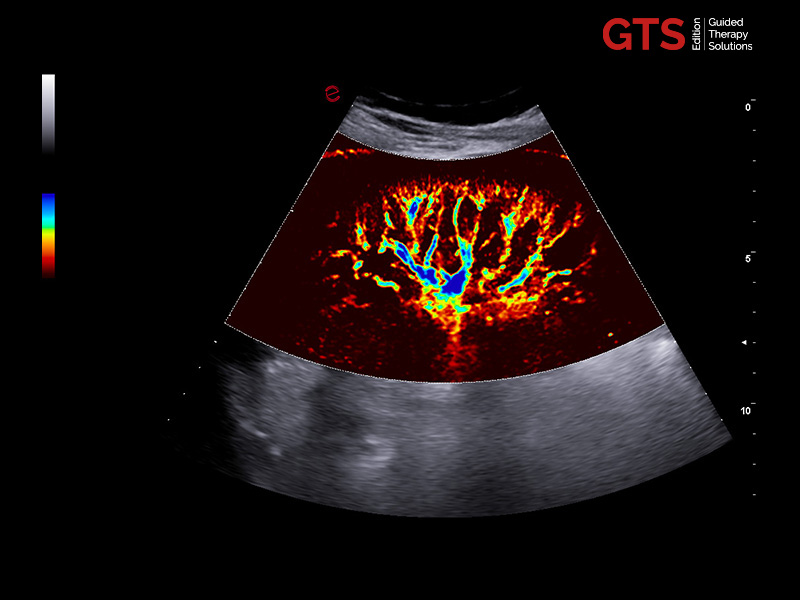

microV shows vascularization and improves the visualization of slow blood flow in tiny vessels.

An adaptive algorithm identifies the blood flow signals and separates them from background tissue and motion artefacts. By eliminating background noise, microV technology enables an advanced hemodynamic evaluation with maximum sensitivity and spatial resolution.

Testis Varicocele under HF linear transducer examination - Micro-vascularization on kidney through microV